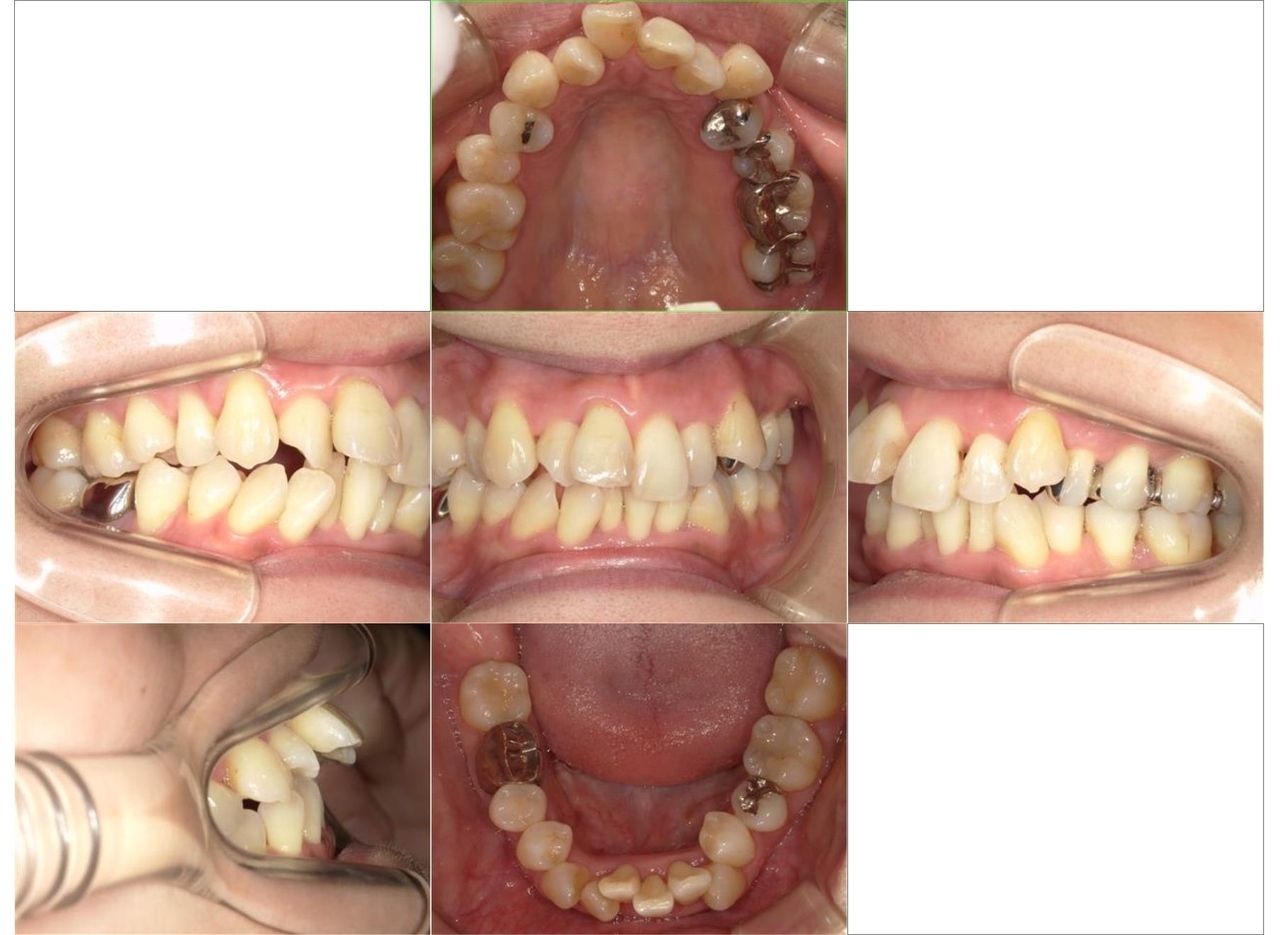

歯ならびの治療を主訴にご来院されました。上顎前歯の突出がみられ、唇が閉じにくく、麺類が食べにくいとのことでした。まず、保険診療で歯周病の治療を行いました。ワイヤー矯正とインビザラインによる矯正治療を説明し、ワイヤー矯正治療を希望されました。まず、歯を並べるためのスペースを確保するため、上顎小臼歯の抜歯を行いました。その後は、レベリング、リトラクション、正中合わせ、コントラクション、アイデアルアーチによる最終調整をしました(専門用語ですみません)術後は、食べ物が食べやすくなったこと、見た目が改善されたことを喜ばれていました。全体的に歯周病の進行が見られるため、今後は歯周病安定期治療による定期的な治療を続けていきます